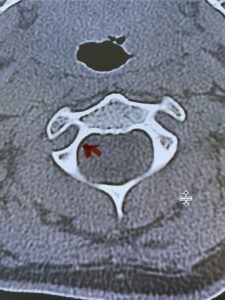

Cervical x-rays revealed a significantly increased atlanto-axial interval (Fig. 5) On review of her imaging studies it was noted that the right C2 isthmus was very thinned by the vertebral foramen (Figs 6a, b, and c) which would make an attempt at placing a C2 pars screw dangerous. A decision was made to perform an occipital-cervical fusion because only possible unilateral fixation and an extensive C1 laminectomy to be performed eliminating a fixation point if a more traditional C1-C2 was performed. Even if C1 lateral mass screws were able to be placed one could only perform a unilateral screw construct fixation to C2. We performed an occipital cervical fusion down to C4 to get enough inferior fixation and C1 laminectomy. The decompression went well. We placed a left unilateral pars screw and bilateral C3 and C4 lateral mass screws. We placed three 12 mm screws in the midline keel (Fig. 7). Postoperatively the patient had all around improvement in her symptoms and did not qualify for rehab. Her post op films at 6 weeks (Fig. 8)

Fig. 6a: Sagittal cervical CT scan demonstrating an abnormally thin right C2 isthmus prohibiting safe placement of screw (red arrow). Notice the vertebral foramen eroding the isthmus bone structure (red dot).

Fig. 6b: Sagittal cervical CT scan demonstrating normal thickness of the left C2 isthmus (red arrow)

Fig. 6c: Axial cervical CT scan demonstrating a very thin right C2 isthmus (red arrow) compared to left side.